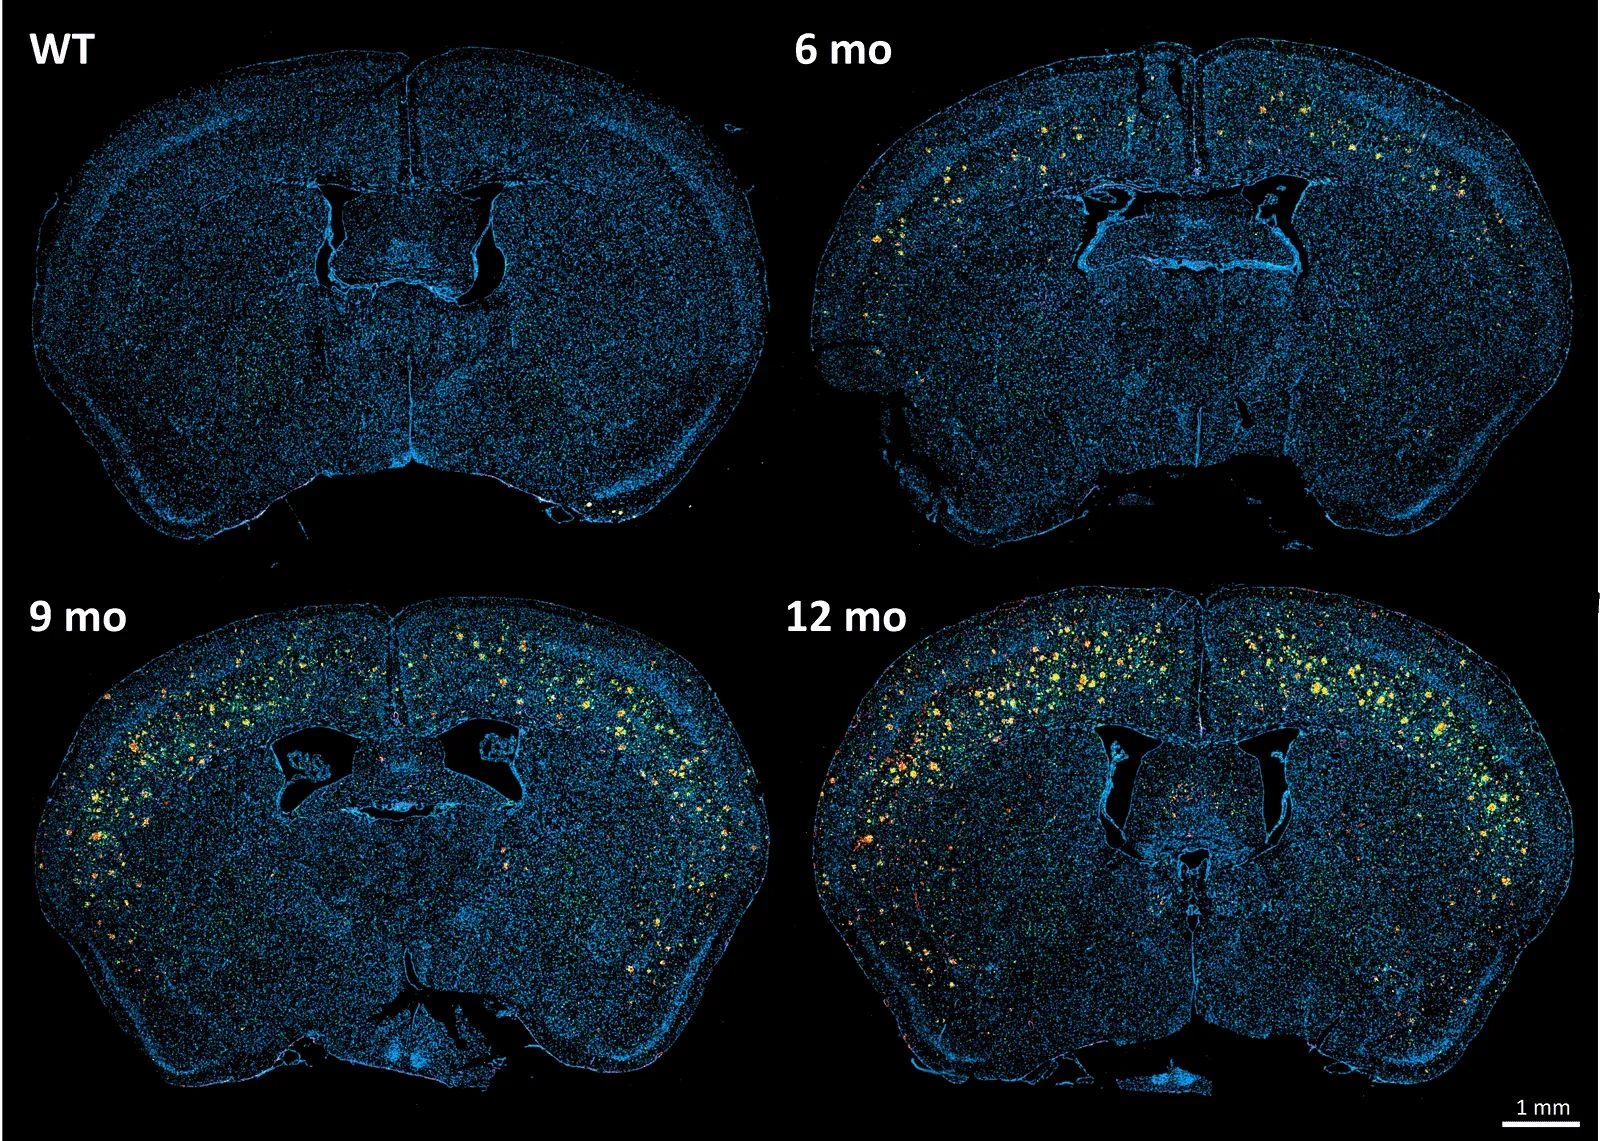

Coupes cérébrales du modèle murin transgénique APP/PS1 (ARTE10) et de souris de type sauvage à différents moments, colorées pour Aβ (rouge), Iba-1 (vert), GFAP (violet) et contre-coloration DAPI (bleu).